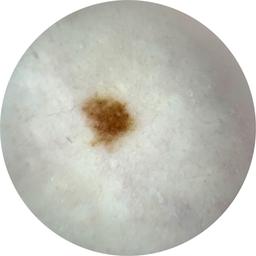

ISIC_3589030

acquisition_day 0

age_approx 45

anatom_site_1 Trunk

anatom_site_2 Anterior trunk

anatom_site_general anterior torso

concomitant_biopsy False

diagnosis_1 Benign

diagnosis_confirm_type single image expert consensus

family_hx_mm True

fitzpatrick_skin_type I

image_manipulation instrument only

image_type dermoscopic

lesion_id IL_6523170

patient_id IP_4878079

personal_hx_mm True

sex female